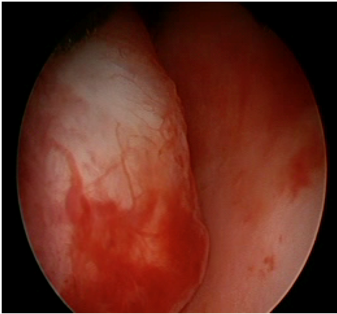

1

Вигляд аденоми передміхурової залози при ендоскопії: вузол аденоми (А) випинає у просвіт сечівника (ПС), перешкоджаючи огляду порожнини сечового міхура та утруднюючи відтік сечі з сечового міхура